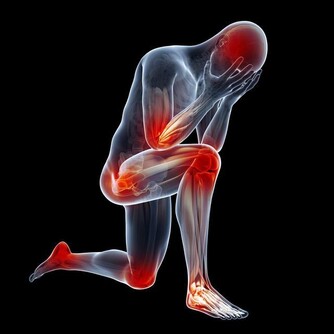

跟癌症、心腦血管疾病相比,關節炎似乎算不上多麼致命的疾患,然而它發作時的痛苦程度,讓所有患者一想起來就心有餘悸。想想手部、手腕、腳部關節疼痛、腫脹、僵硬的滋味吧,你一定不會喜歡的。

可是,如果已經罹患關節炎了,該怎麼辦呢?畢竟,患關節炎的人不在少數。這時候,我們需要做的就是減少關節炎發作的頻率,這不是不可能的。

研究已經發現,補充某種維生素,有助於緩解患者的關節疼痛,甚至使其完全消失。這種神奇的維生素,就是維生素C,它對類風濕性關節炎患者尤其有效。

維生素C大家可能都不陌生,它也被稱為抗壞血酸,但它在防止類風濕性關節炎方面的功效,大家可能就不清楚了。

由於維生素C是一種天然抗氧化劑,所以可以降低炎性細胞因子水平,並防止關節破壞,因而有助於減少關節的疼痛、僵硬和腫脹。

當醫生每週兩次,給因為關節炎而疼痛的患者靜脈注射維生素C,持續四周之後,他們的疼痛消失了。而另外一些研究表明,維生素C水平低的人,出現類風濕性關節炎的可能性,比體內維生素C水平充足的人,要高出三倍。